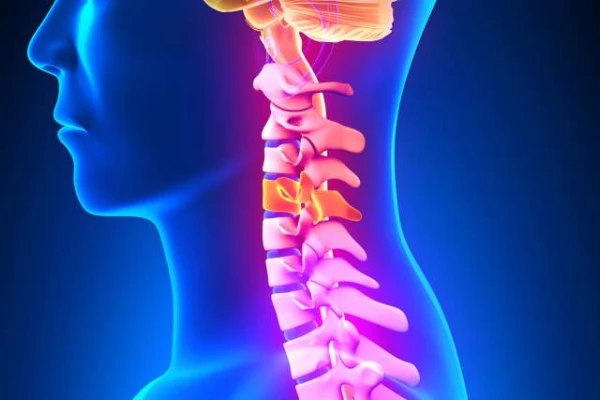

درمان لیزری دیسک کمر چگونه است؟

جراحی لیزی عمدتا در بیمارانی انجام می شود که پارگی واضح در دیسک کمر ندارند. این بیماران برجستگی هایی در دیسک دارند که مختصری فشار روی عصب سیاتیک برایشان ایجاد کرده است، این افراد اغلب جوانانی هستند که دیسک های آبدار غیر دژنره دارند، یعنی دیسک هایی که سیاه نشدند در ام آر آی، بهترین پاسخ را به درمان جراحی با لیزر می دهند.